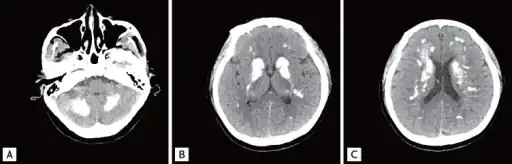

a-c)Brain computed tomography shows diffuse symmetric parenchymal calcifications

a-c)Brain computed tomography shows diffuse symmetric parenchymal calcifications Individual with idiopathic hypoparathyroidism-diffuse osteosclerosis, capsular ossification around bilateral hip joints arrow, ossification of bilateral iliolumbar ligaments arrow, irregular bony excrescences arrowhead, subtle calcification of the right sacrospinous ligament open arrow